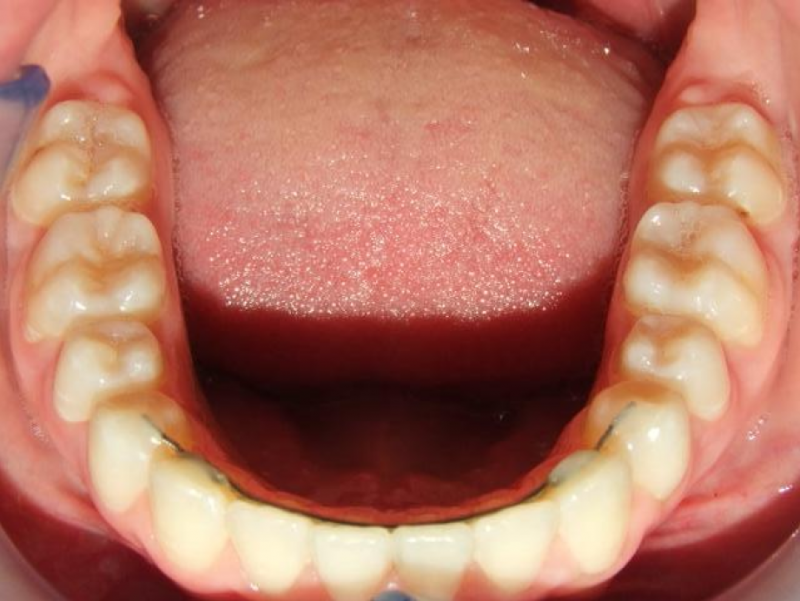

eindfoto

Beschrijving

Leeftijd bij aanvang: 9 jaar

1-6 Bonded Hyrax + volledig vast onderkaak & TransForce

7-13 Twin Block

14-26 volledig vast boven- en onderkaak + TPA

Leeftijd bij retentie: 11 jaar